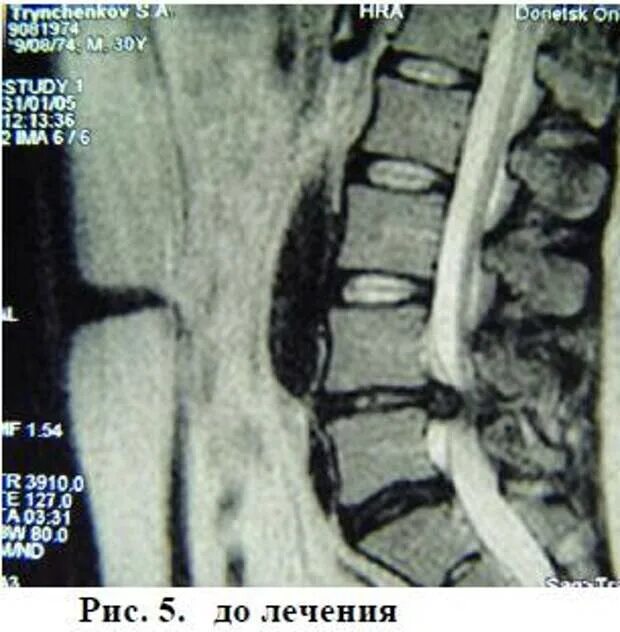

Грыжа диска мрт